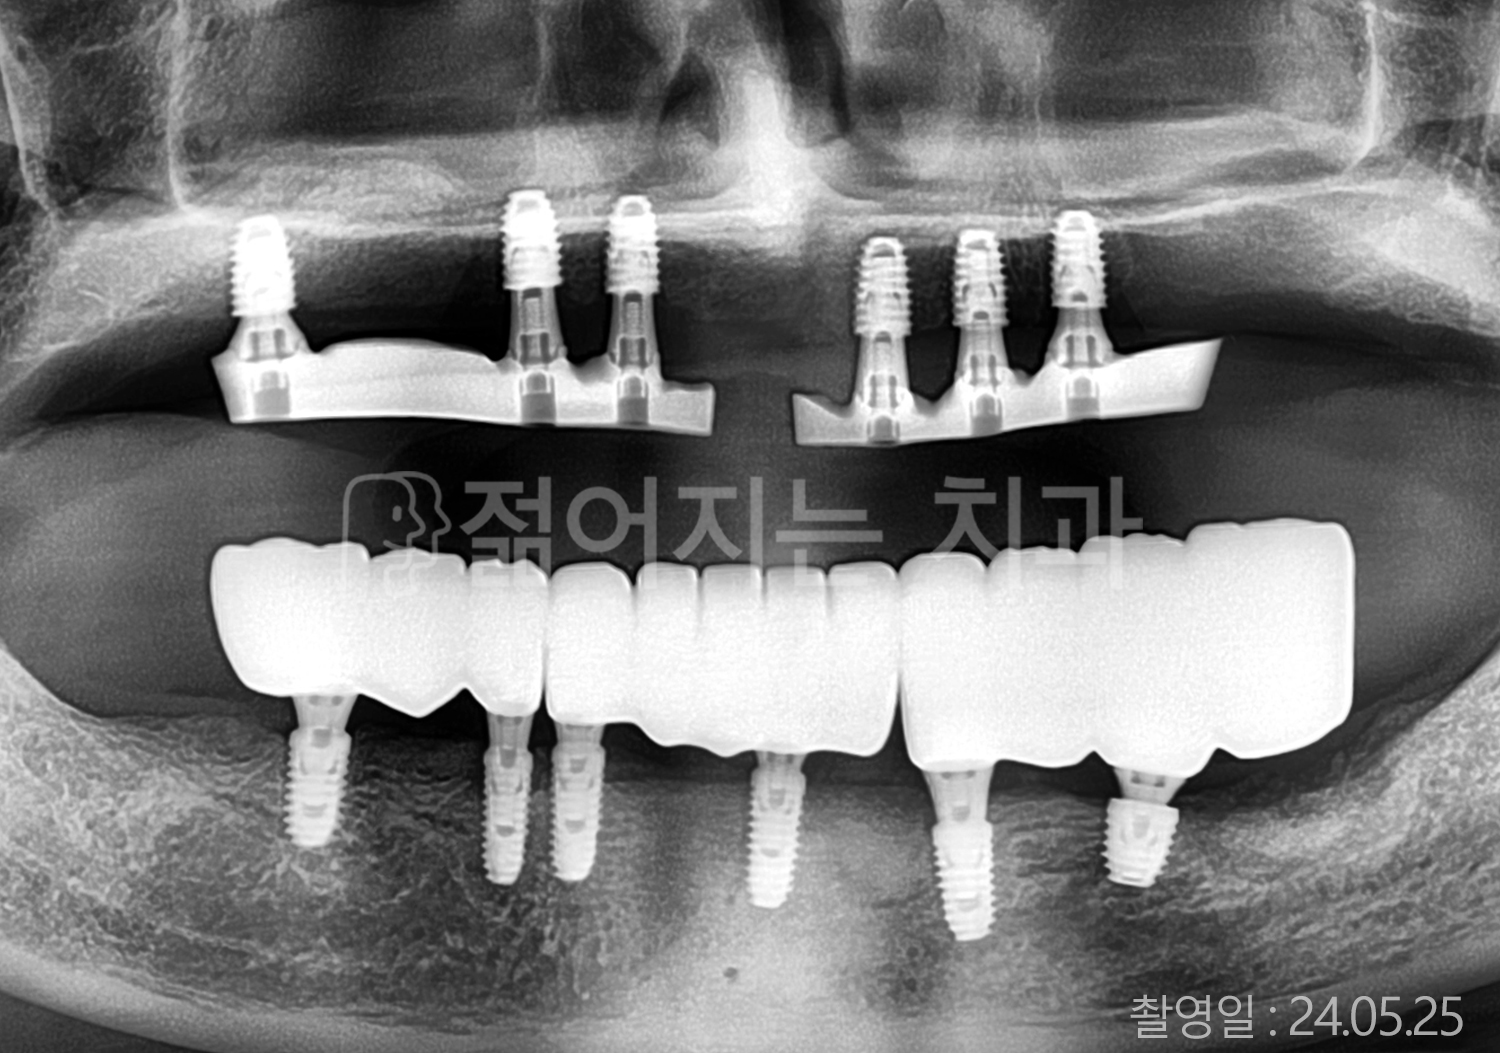

• 40대 전체치아 10개 이상 임플란트

• 50대 전체치아 10개 이상 임플란트

• 50대 고혈압, 당뇨, 고지혈증 전체치아 10개 이상 임플란트